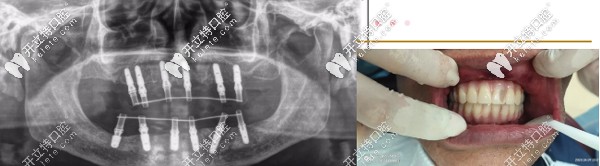

針對(duì)魏叔年齡大、口腔條件不佳的復(fù)雜特點(diǎn),熊小明院長(zhǎng)為魏叔定制ALL-ON-6即刻種植方案,拔掉剩余松動(dòng)殘牙,全口種植12顆,修復(fù)24顆牙。

▲魏叔種牙后